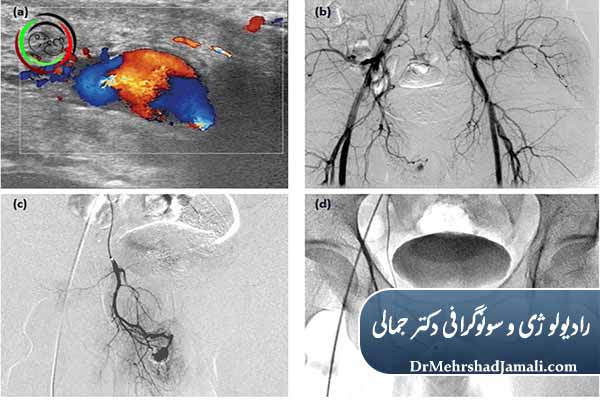

آمبولیزاسیون پنیس (Penile Embolization) یک روش کمتهاجمی و غیرجراحی است که برای درمان نوع خاصی از اختلال نعوظ، بهویژه نشتی وریدی (Venous Leak) استفاده میشود.

-

رگهای وریدی غیرطبیعی که باعث خروج سریع خون از آلت تناسلی میشوند

با مواد مخصوص پزشکی بهصورت هدفمند مسدود میشوند

و در نتیجه، نعوظ پایدارتر و با کیفیت بهتر ایجاد میشود

بررسی جریان خون آلت تناسلی

انجام آمبولیزاسیون

با هدایت تصویربرداری پیشرفته

انجام تحت هدایت دقیق آنژیوگرافی